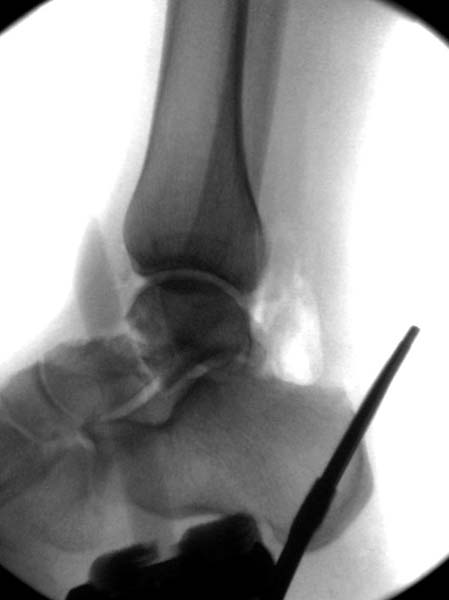

Трудно выбрать приоритет, когда имеется одинаковые по значимости, по сложности повреждения и с вовлечением различной локализации. У пожилых переломо-вывих головки бедра можно было бы проигнорировать, но у молодых такое решение привело бы к катастрофе, и поэтому приоритет первичной фиксации отдали решению переломо-вывиха таранной кости и головки бедра.

Больная стабильная после хирургических мероприятии и получив добро, приступили к закрытому вправлению таранной кости с укладкой наружного фиксатора. Затем укладка больную на бок и открытый остеосинтез перелома-вывиха головки бедра.

После спадения отека на стопе произведена фиксация тарана. Кстати, коллеги пересмотрели первоначальную консультацию по позвоночнику и на двух уровнях провели фиксацию. Из-за длительного постельного режима без нагрузки таз не стали оперировать...